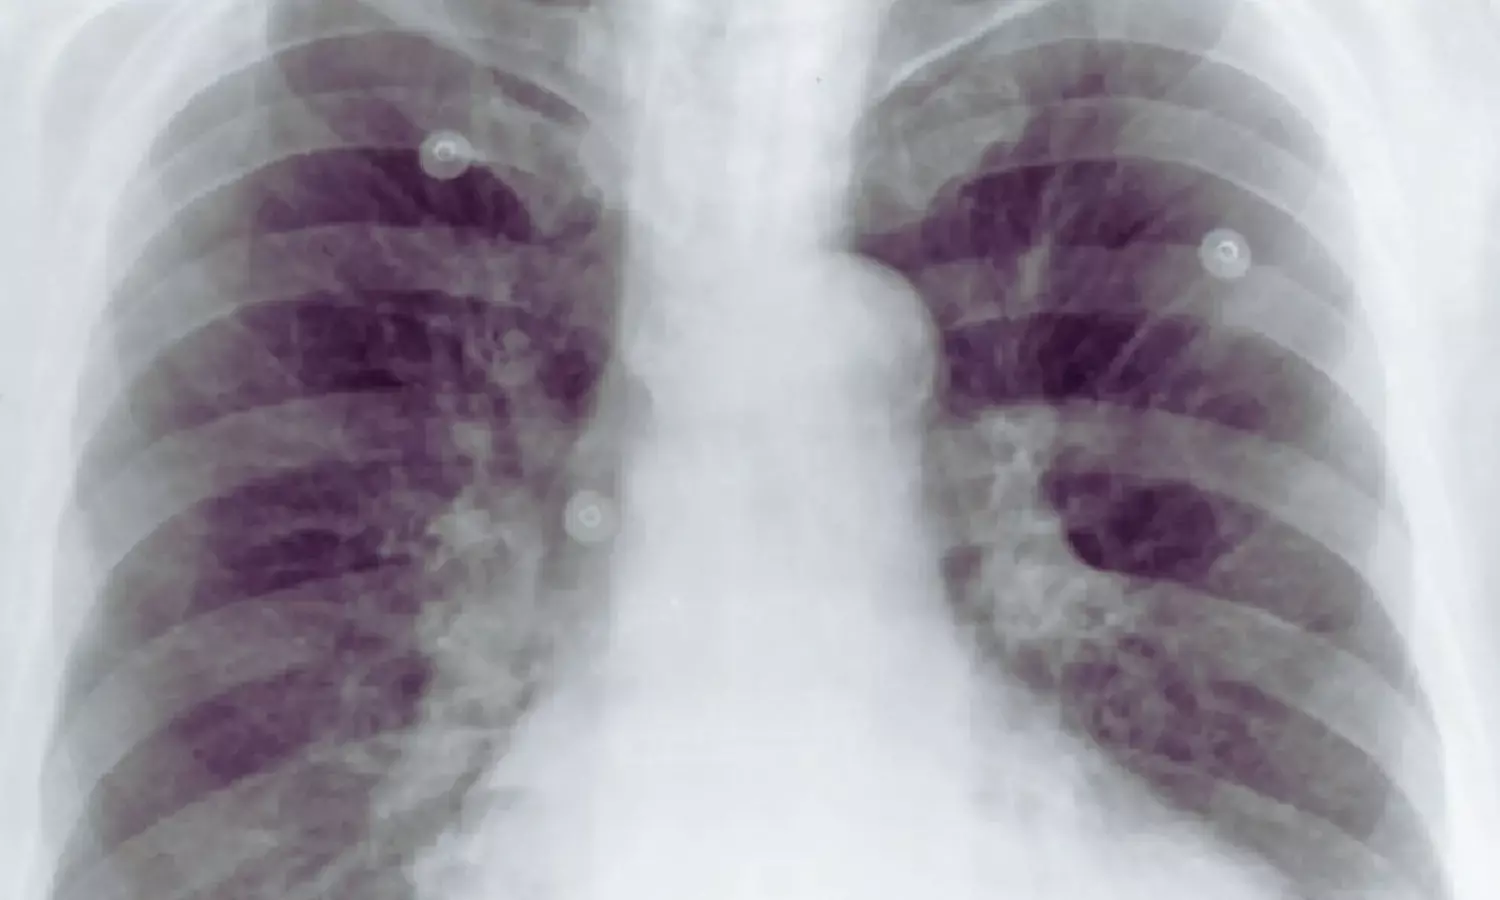

Finland: Aortic calcifications (ACs) visible on routine chest radiographs may signal worse survival prospects for patients undergoing minor lower limb amputation, a study published in JVS: Vascular Insights has shown.

The investigators conducted a single-center, retrospective observational study involving 383 patients who underwent minor amputations below the ankle between 2007 and 2020. All participants had received an upright anteroposterior chest x-ray within three months before surgery. The amputations were performed primarily due to complications of peripheral arterial disease and diabetes—conditions strongly linked to systemic atherosclerosis.

Two researchers independently reviewed the preoperative chest radiographs to determine the presence and extent of aortic calcifications. Calcifications were graded using three classification systems—the Symeonidis system, the Tian system, and a newly introduced AV classification—categorizing findings as none or mild, moderate, or severe based on the size and distribution of calcified deposits. Severe calcification was defined as circumferential or near-circumferential involvement of the aorta.

• A total of 62.1% of patients had detectable aortic calcifications on preoperative chest x-ray.

• Severe AC was present in 21.9% of patients.